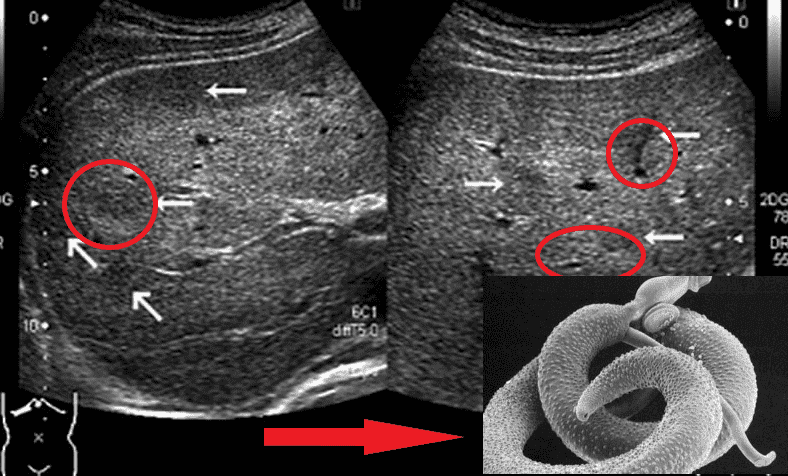

Bewegungen von Parasiten im Darmlumen

Vertreter von Helminthen, die lebenswichtige Organe befallen, sind Taenia solium, Echinococcus granulosus und Trichinella spiralis. Echinococcus ist das Larvenstadium eines Helminthen aus der Gattung Echinococcus. Dies sind bei Weitem nicht alle Arten von Parasiten, die einen Menschen töten können.